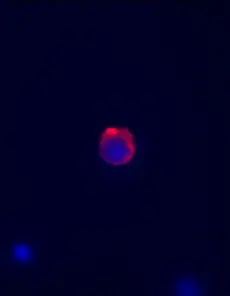

Example images from patient blood samples

Cluster of mesenchymal CTCs - breast

Examples of Portrait+ CTC staining kit samples